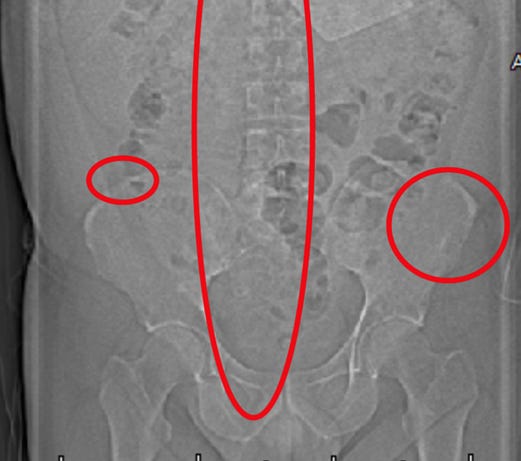

Mon patient a subi plusieurs examens d'imagerie révélant la présence de micropuces implantées. Ces emplacements correspondaient aux zones de torture les plus sévères. Ci-dessous, vous pouvez voir une micropuce entourée :

Il y en a un autre à la base du sacrum :

Une autre fracture est présente au niveau de la crête iliaque droite.